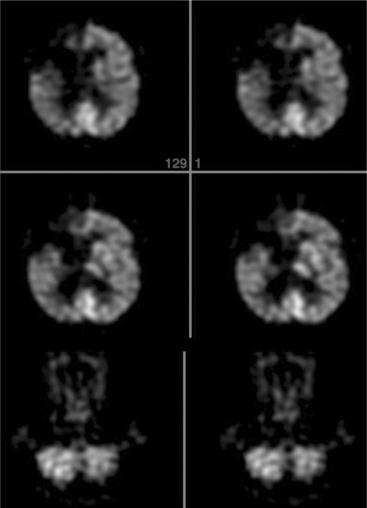

Positron emission tomographic (PET) imaging has been of great benefit in advancing the understanding of the pathophysiology of cerebrovascular disorders. PET imaging allows for the detection of stroke earlier and with higher sensitivity than anatomic imaging with either MRI or CT. Furthermore, PET imaging has been useful in evaluating the extent of the functional damage because areas not immediately affected by the infarct may show hypometabolism or decreased blood flow. Initial stroke severity has been shown to correlate with the initially affected volume as determined by PET, whereas neurologic deterioration during the first week after stroke correlates with the proportion of the initially affected volume that infarcted, and functional outcome correlates with the final infarct volume. Crossed cerebellar diaschisis is seen as hypometabolism and hypoperfusion in the cerebellar cortex contralateral to the site of the infarct and usually occurs during the first 2 months after infarction (Fig. 32-15).66

Figure 32-15 Fluorodeoxyglucose PET scan of a patient after embolic stroke in the distribution of the right anterior cerebral artery. There is severely decreased metabolism in the right frontal lobe extending to the midline. There is also crossed cerebellar diaschisis with decreased metabolism in the left cerebellum. (Reprinted from Newburg AB, Alavi A: The role of PET imaging in the management of patients with central nervous system disorders, Radiol Clin North Am 43(1):49-65, 2005.)